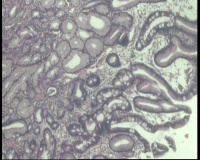

镜下见十二指肠粘液腺明显增多,排列密集,中心有少量平滑肌组织间隔,局灶腺体扩张,是十二指肠息肉还是报十二指肠腺腺瘤?

图2